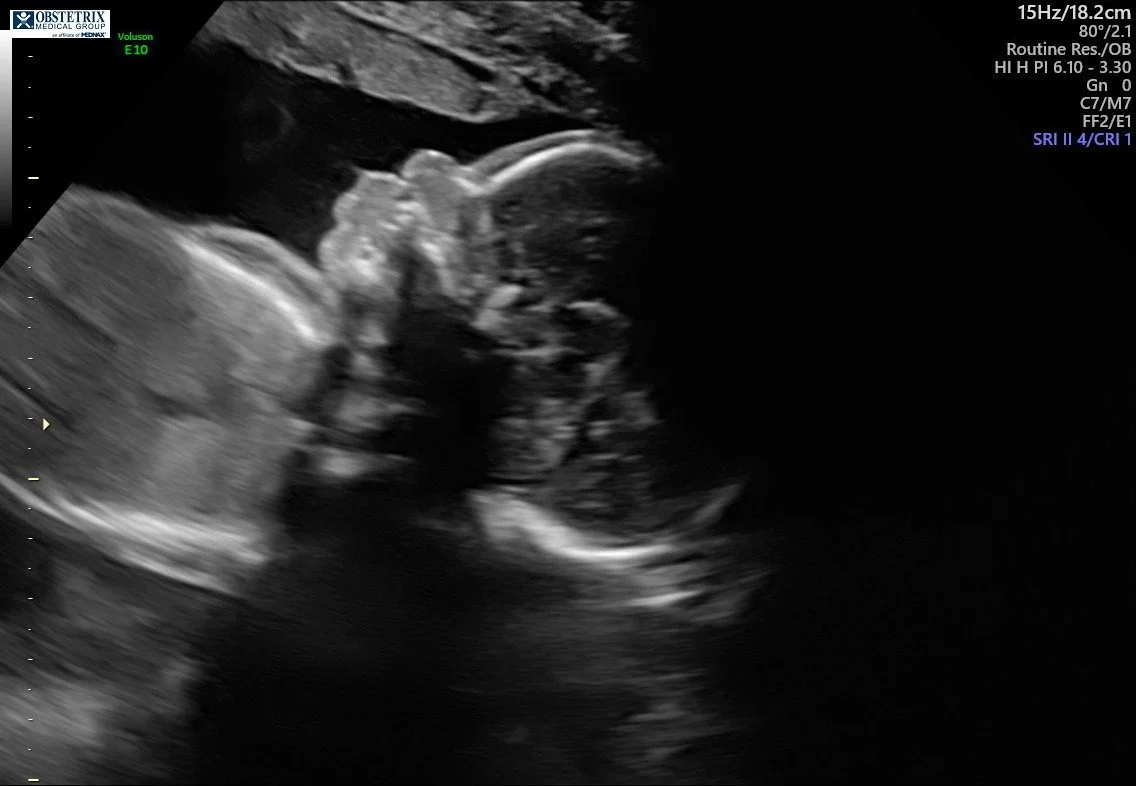

I’m measuring right on track at 23 weeks. Our baby weighs 1 lb 3 oz—WOW. I cannot believe our baby already weighs over a pound. And the best news of all? My cervix is holding like a rock. PRAISE BE!

We also got to see our little pumpkin in live 3D, which was such a special moment. Our baby is getting stronger and stronger every single day—and I know this because the kicks and punches are becoming more powerful by the day. It’s truly the best feeling in the world… until I’m laying down trying to go to sleep, LOL. Baby definitely likes to be active while mommy is resting.